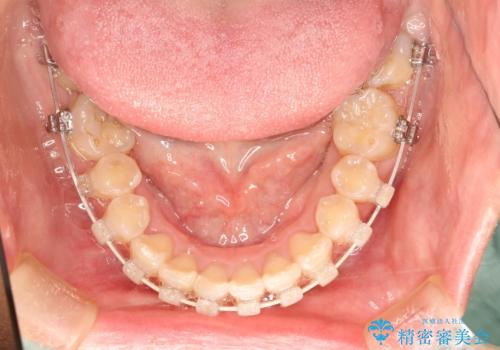

- ハーフリンガル

- 1年8ヶ月

- 上顎の両側第1小臼歯抜歯による抜歯矯正を計画した。